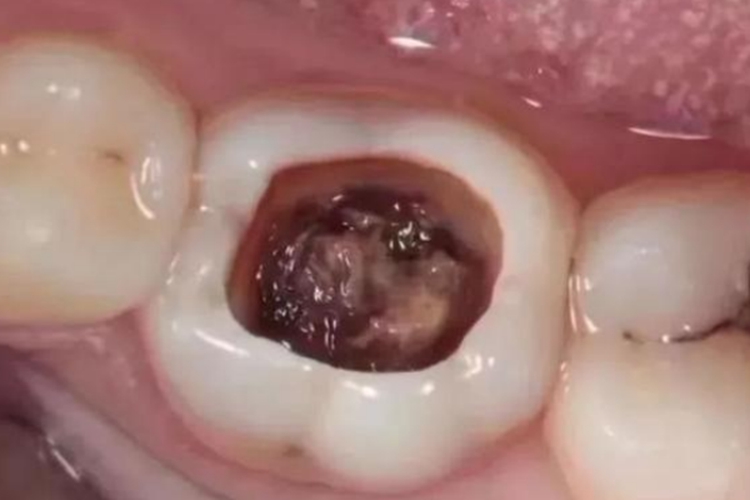

当牙齿坏了一半且内部空洞时,需要根据具体情况采取相应的措施,比如牙髓未受到影响的话,可以进行补牙治疗。

1、牙髓未受影响:如果牙髓尚未受到感染,且剩余的牙体组织足够坚固,可以通过补牙来修复。先去除龋坏组织,然后用填充材料填充空洞,费用一般在几百元。

2、牙髓轻度感染:若牙髓有轻度感染,可能需要进行根管治疗,清除感染的牙髓,对根管进行消毒和填充,最后再进行补牙或牙冠修复,根管治疗加上牙冠的费用可能在数千元。